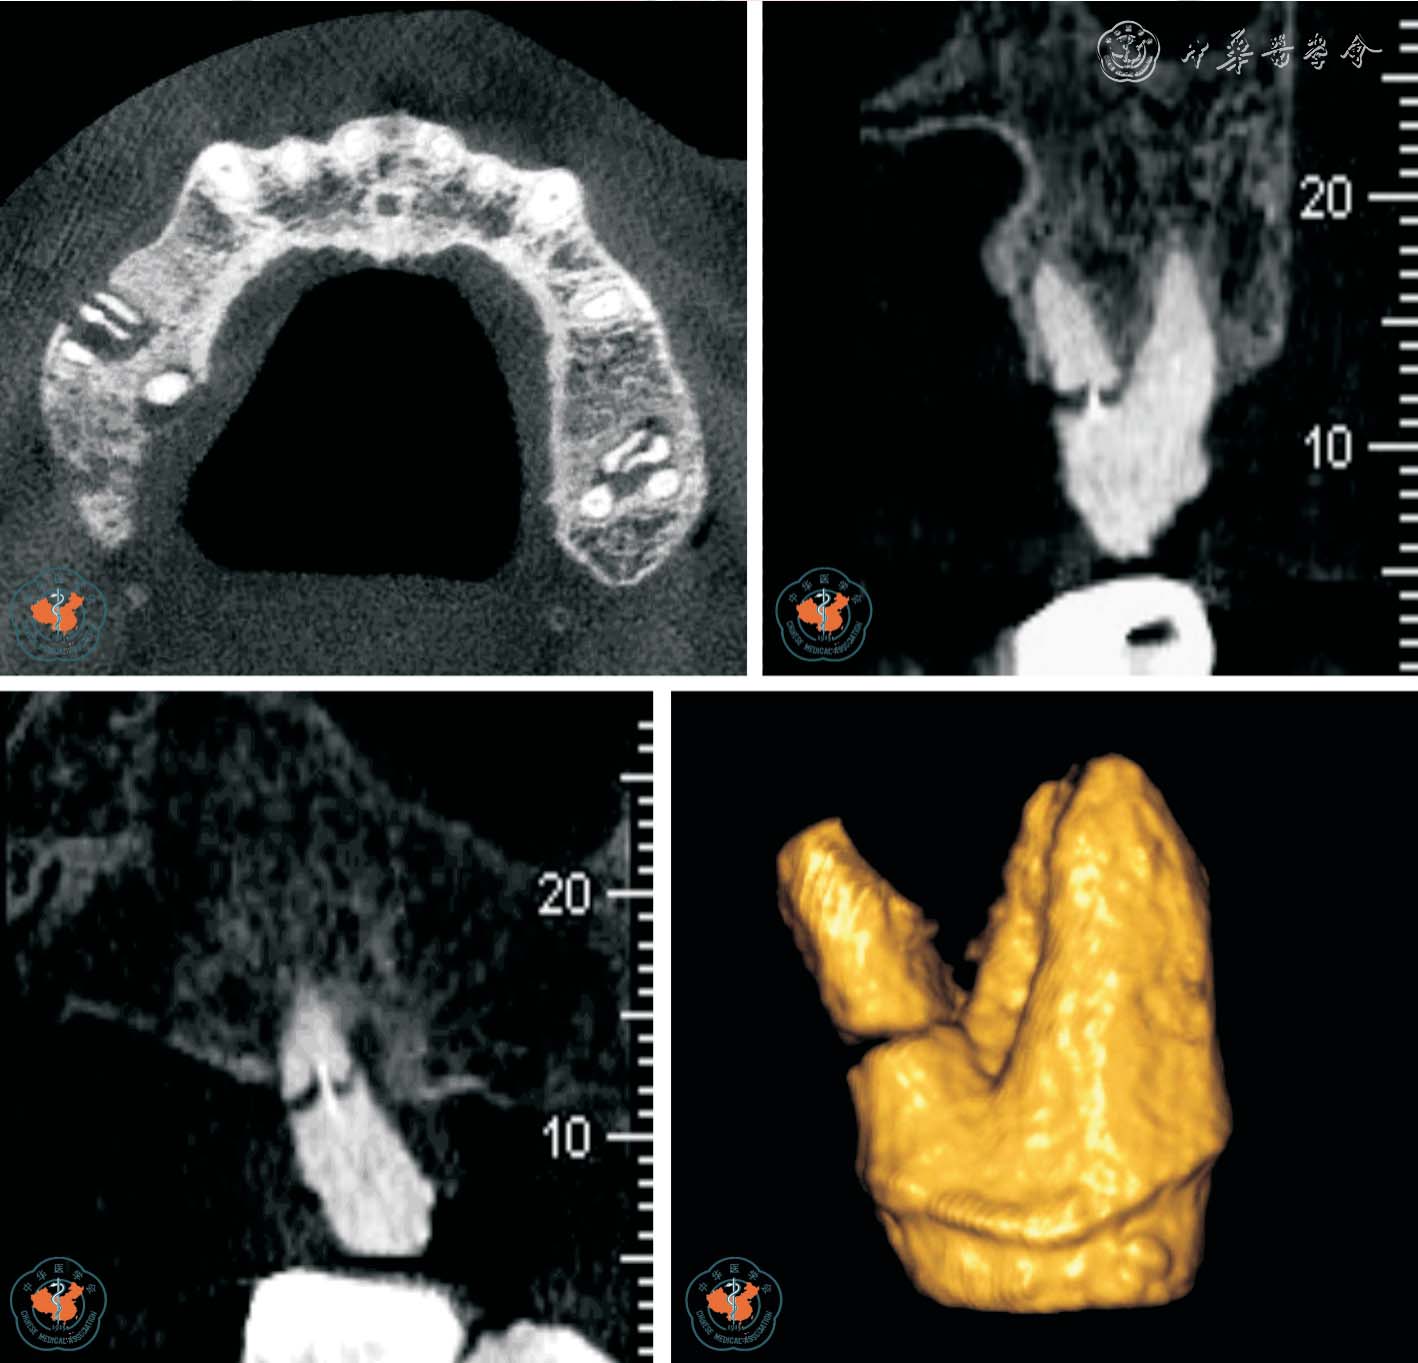

1. 正确判断根管数目: 根管数目的正确判断是根管治疗成功的主要因素之一。 Baratto Filho 等11采用体外研究、临床研究和CBCT 三种方法分析了上颌第一磨牙的根管解剖。 体外研究表明,140 颗离体牙中67.12%存在第四根管,其中1 例有7 个根管,存在第四根管的磨牙中92.58%第四根管位于近中颊根。 临床研究表明,53.26%及0.35%的磨牙分别存在4、5、6 个根管, 并且95.63%发生于近中颊根。 CBCT 研究表明,1.85%、37.05%、1.85%的磨牙分别存在2、4、5 个根管。 同时CBCT 对变异根管的发现和定位具有重要意义。 临床医师在根管治疗术前及术中可随时调用和调整CBCT 局部三维重建图像,从不同角度及层面观察根管的融合和分支情况,了解根管的形态、数目、走向、根尖处根管的位置是否融合等,是指导复杂根管系统牙齿治疗时的重要影像手段(图1 ~2)。

图1 CBCT 轴位显示左上颌第一磨牙5 个根管,其中侧支根管未根冲

图2 CBCT 轴位、VR 及MPR 重建冠、矢状位图像显示上颌中切牙变异根管